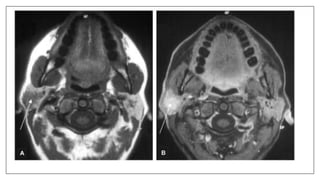

Metal artifacts: Braces

Braces may cause an artifact distant from the source. The axial proton density

and T2-weighted images exhibit horseshoe shaped artifacts. Note it is much

subtler on the T2 image.